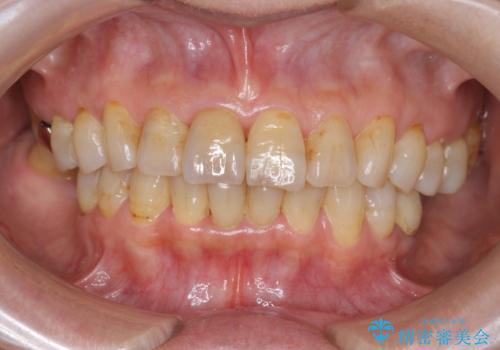

- 前歯を転倒で受傷し、審美性の回復を求めて来院されました。

近医で暫間的なコンポジットレジン修復が為されていましたが、色調に不満があるということでした。

色調の変化が少なく、長期的な予後を見込めるジルコニアクラウンで天然歯を模した審美性の回復を計画します。